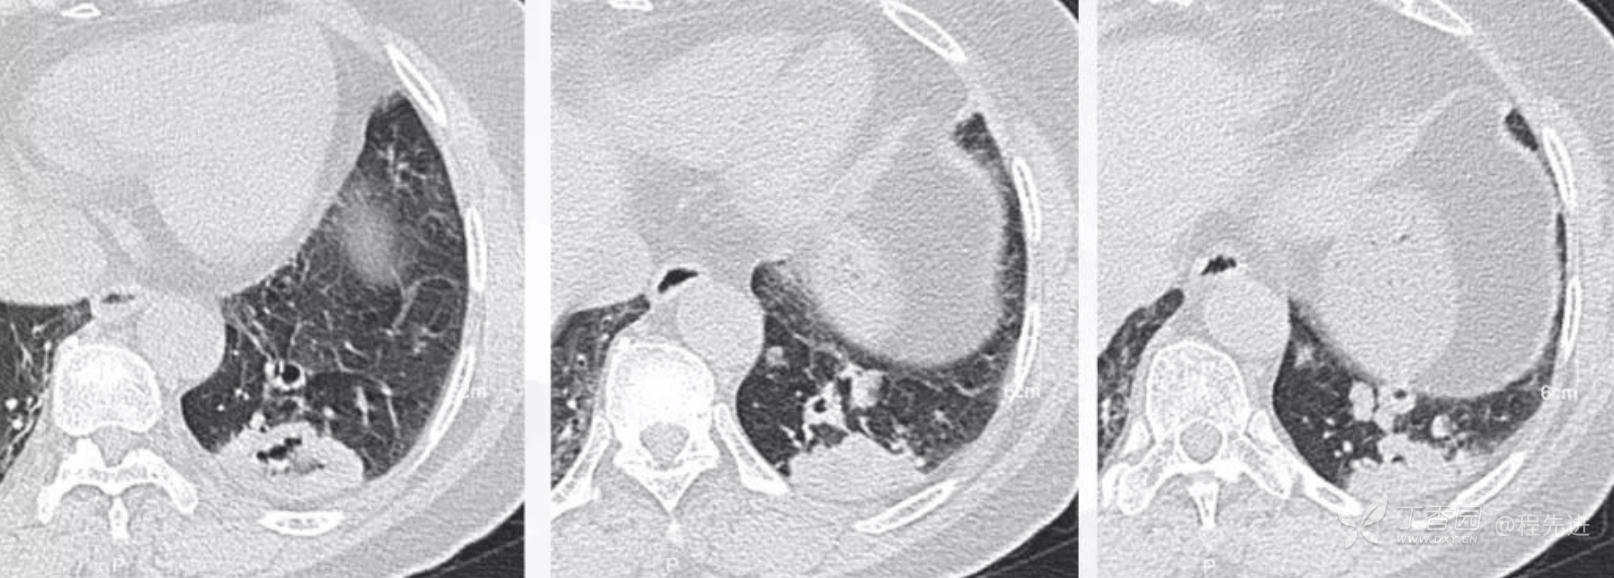

冠状位重建